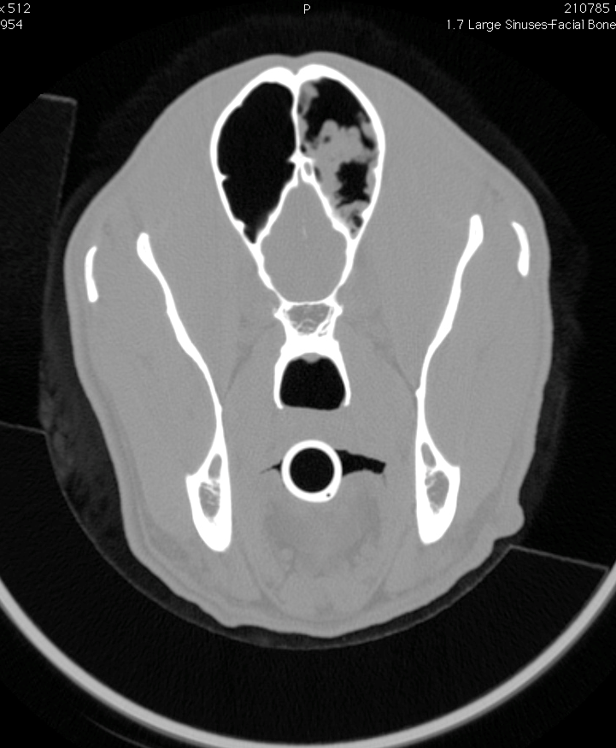

What is the issue here?

Aspergillosis into frontal sinuses